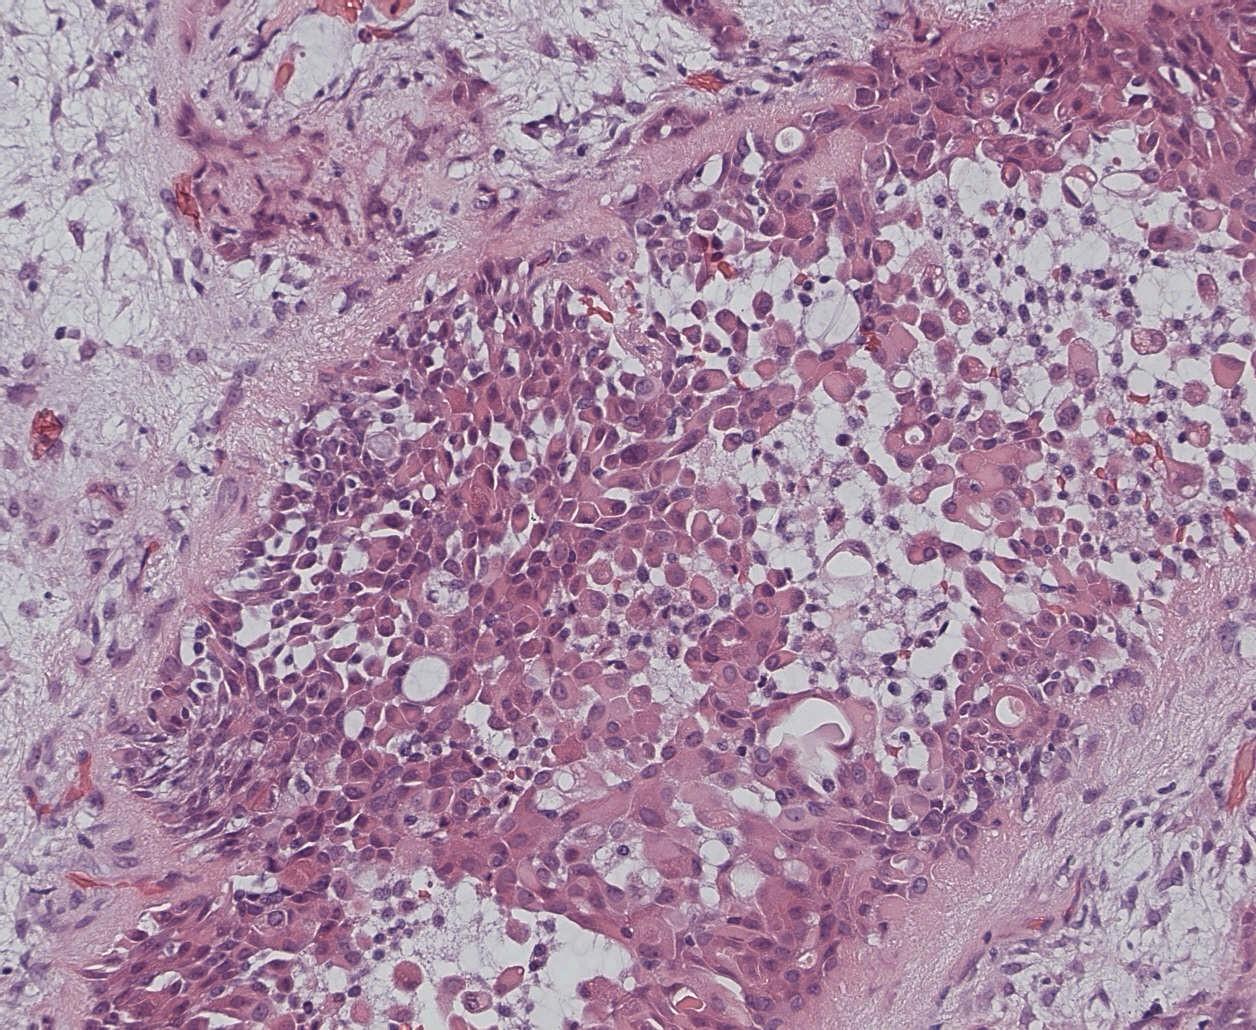

Sinonasal NK/T cell lymphoma

 Broad morphological spectrum

 Polymorphic with atypical lymphoid cells

 Plus background of other cells (neuts eos)

 Pale to clear cytoplasm

 Angioinvasion

 Geographic necrosis

 CD56, variable for T cell markers (CD2)

 EBV related

a, Proliferation of small to large, pleomorphic lymphoma cells

b, Lymphoma cells are invading a vein (arrows)